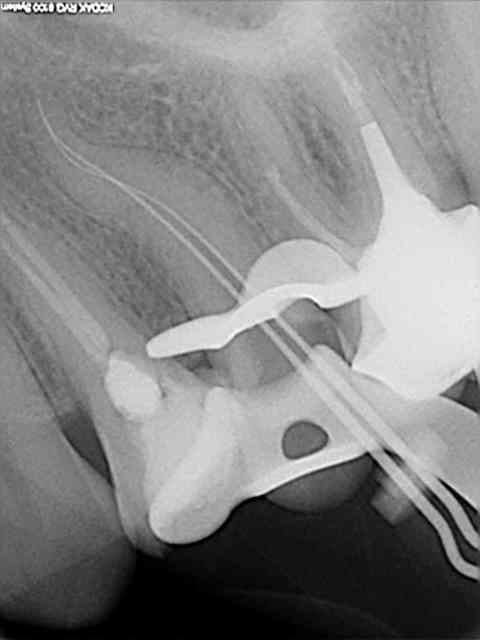

alors ok voilà un cas bien foiré:

Une des premières fois que j'ai utilisé un contre-angle avec localisateur intégré.

Je me suis cru à l'abri avec le contrôle du torque sur l'instrument en temps réel.

Les diodes se sont alummées au début de la descente dans le canal et j'ai voulu continuer à avancer avec l'instrument en rotation malgré un cathétérisme manuel pas réalisé sur la totalité du canal.

Fracture , puis initiation de fausse route en essayant de passer à coté manuellement.